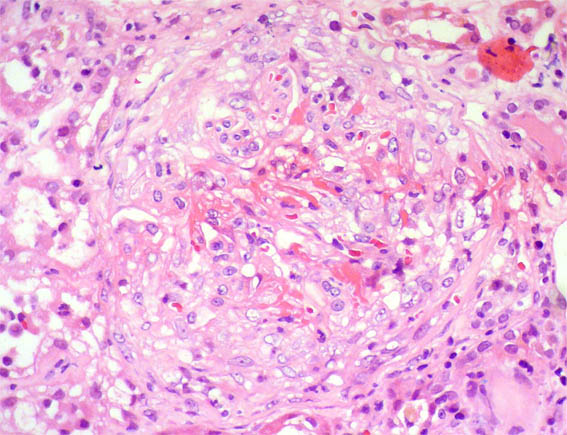

Figura 2. H&E, X400.